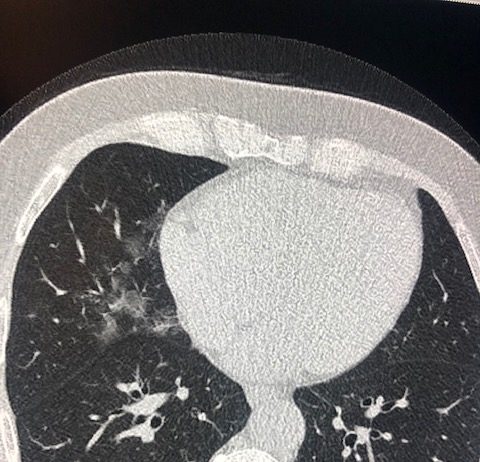

Uomo 57 anni, nessuna comorbidità nota.

Febbre e tosse non produttiva.

Leucocitosi. Insufficienza respiratoria ipossemica e ipocapnica.

Sospetto contatto con soggetti zona rossa. Tampone positivo NCOV 19.

HRTC Torace